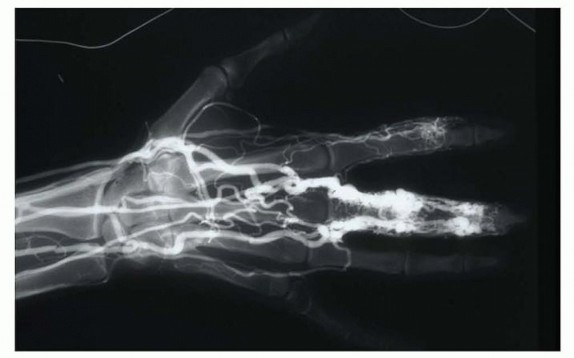

Plain radiographs of the digits and handsPhleboliths (in 6%) and bony hypertrophy may be noted.20,24There may be evidence of a soft tissue mass or signs of bone erosion or destruction of the cortical surface, which is seen in about 6% of patients with hemangiomas.24Doppler ultrasonic flow detection is a noninvasive study that does not require the use of contrast.It has been used to confirm high-flow anomalies and to help differentiate between hemangiomas and malformations.31 Doppler ultrasonography will show these lesions to be monophasic with low-flow velocity averaging 0.22 kHz.30Computed tomography with contrast enhancement may show bony involvement of the tumor, especially in type A high-flow malformations.32MRI/magnetic resonance angiography (MRA) can be used to evaluate the site, size, flow rate, and characteristics of the lesion as well as involvement of contiguous structures.32It may be used to determine whether a malformation is low flow or high flow and can also distinguish between dense parenchymal lesions and malformations with large vascular channels.14It can also be used to evaluate glomus tumors, which have a high signal intensity on T2-weighted spin-echo MRI or after gadolinium injection.21MRI has a sensitivity of 90% and a specificity of 50% for glomus tumors, so that it cannot be used as the only diagnostic study for glomus tumors, especially if they are less than 2 to 3 mm in size.2Hemangiomas will appear as well-circumscribed mass lesions that enhance with gadolinium and will have a high T1 signal secondary to infiltrative margins and fatty tissue overgrowth as well an extremely high,heterogeneous T2 signal. A serpentine pattern in the mass may also be seen on MRI.36MRA may be performed at the time of MRI to evaluate lesions in patients who are unable to undergo angiography secondary to renal problems or contrast allergies. It can be used to define the anatomic extent of lesions and their relationship with the surrounding tissue. It can be used to evaluate for both arterial andvenous tumors without contrast enhancement.8Technetium 99m red blood cell perfusion and blood pool scintigraphy will show increased activity on early and late blood pool images with increased perfusion in hemangiomas and may be useful in their diagnosis.36 Angiography is the gold standard evaluation of certain tumors, including vascular malformations. No longerroutinely used for diagnosis of a lesion, it is used as an evaluation for operation or embolization.32 It may showa cluster of anomalous arterial branches with multiple communications with venous trunks draining the site of involvement.22Closed venous angiography uses contrast injected into the venous system distal to a proximal arterial tourniquet applied on the upper arm. Contrast is injected into the exsanguinated extremity distal to the tumor,and radiographs are taken as the vascular tumor fills to get an accurate assessment of the anatomy.20 Arterial angiography is performed through a stick into the femoral artery with a catheter that is fed into the involved extremity. Dye is then injected and both the arterial and venous phases of circulation are evaluated. This can be used to evaluate the size of the tumor, locate the feeding vessels, and embolize feeding vessels beforeoperation (FIG 12).20